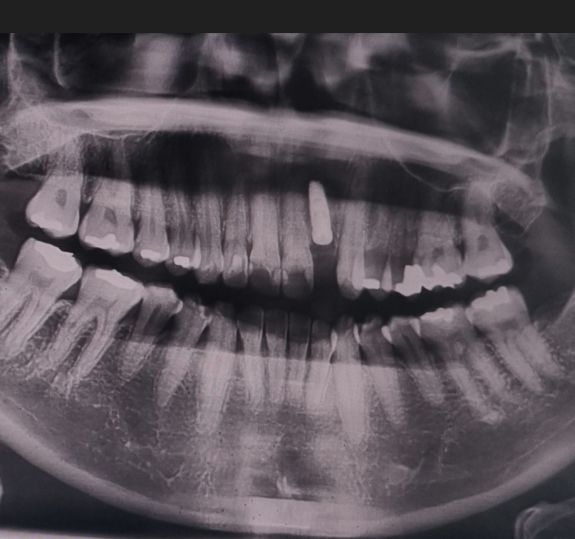

저의 경험상 항암치료를 하면 피부, 항문, 관절통 뿐만 아니라 치아에도 엄청 영향을 주는 것 같아요. 독한 항암제 성분이 우리 입 속 침에도 남아있어서 그런 것 같습니다. 하지만 항암치료를 하면 감염이나 지혈 등에 문제가 발생할 수 있기 때문에 치과치료는 간단한 스케일링도 하지 말라는 안내를 받습니다. 그래서 보통 항암 시작 전에 시간적인 여유가 있다면 치과진료를 미리 받으라고 안내를 받는데, 저는 암수술과 항암치료 시작이 너무 촉박하게 진행되어서 아무런 준비를 못하고 항암을 시작하게 되었습니다. 저는 아이스항암을 6차 진행했는데, 4차까지는 구내염과 잇몸통증으로 고생을 했었고 5차부터 치아 시림 등 통증이 발생해서 막판에 고생을 많이 한 케이스입니다. 그때까지는 주치의 선생님이 치과치료를 하면 안 된다고 하셨었고, 이가 많이 아픈 것은 아니라서 계속 참아왔고 10월에 항암치료 종료 및 1월 추적검사 1차때 피검사 결과 등을 바탕으로 주치의선생님께 치과치료 허락을 받았습니다.

- 사진을 찍어 정확한 치아 상태 파악합니다.

- 사진을 보면서 진료를 진행할 의사에게 설명을 듣습니다.